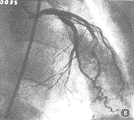

众多学者认为:冠心病冠脉病变以左前降支最多见,其次是右冠及回旋支(图1,2),本组病变左前降支占49.6%,右冠28.5%,回旋支20.3%,而左主干仅有6例,与文献[1,2]报道相一致。

图2 右冠脉多处偏心重度狭窄,主干呈串珠状